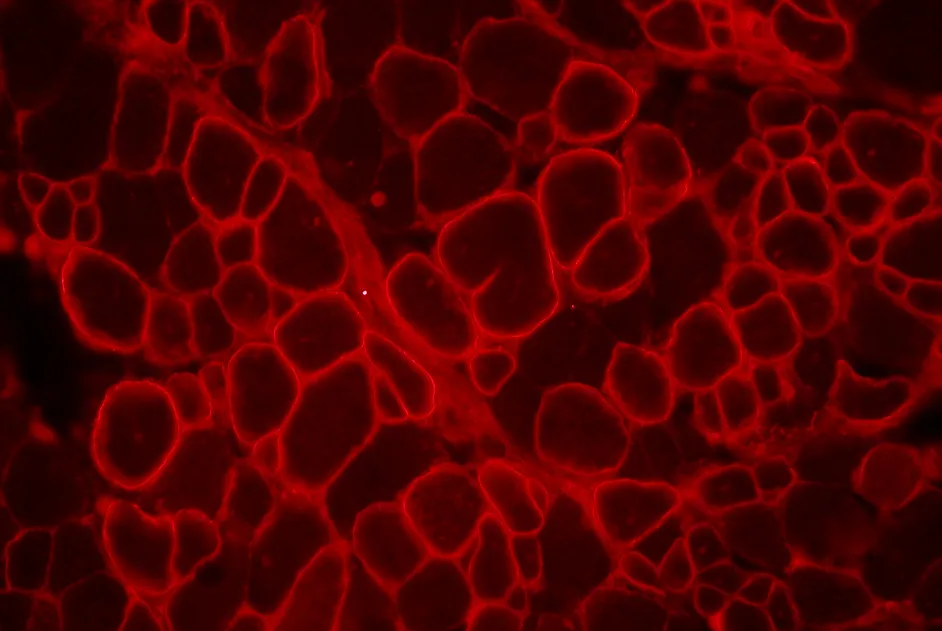

Dans un article publié en juin 2013, une équipe de l’Institut de Myologie (Paris), soutenue par l’AFM-Téléthon, a montré dans une souris modèle que le virus adéno-associé (AAV) transportant un U7 qui vise le saut d’exon de la dytrophine reste dans les fibres musculaires traitées alors qu’un U7 sans action sur la dystrophine disparait au bout de 3 mois. Toutefois, la restauration de la dystrophine obtenue grâce à l'AAV-U7-DMD diminue fortement au bout de 12 mois. Les auteurs suggèrent qu'il faut injecter une dose optimale d’AAV-U7 visant à restaurer la dystrophine, pour stabiliser les fibres traitées et maintenir l’effet de ce traitement à long terme.